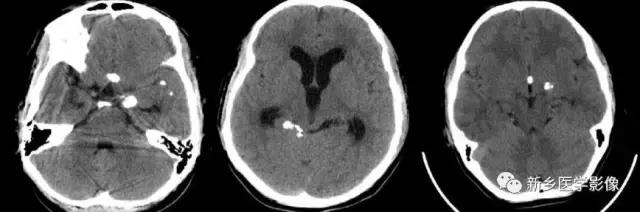

三、脑结核病

结核性脑膜炎患者后期,约半数在靠近颅底部、鞍区附近出现散在钙化斑点,区别于其他细菌性脑膜炎。

脑内结核瘤早期,中线干酪样坏死区可出现斑点状钙化,增强扫描时周围呈环状强化,与病灶中心点状高密度钙化,构成典型的结核瘤的“靶样征”,是识别结核瘤的重要证据;

晚期,整个结核瘤可出现钙化,呈结节状,也可仅其壁部分出现钙化,呈断续之环状或蛋壳状。